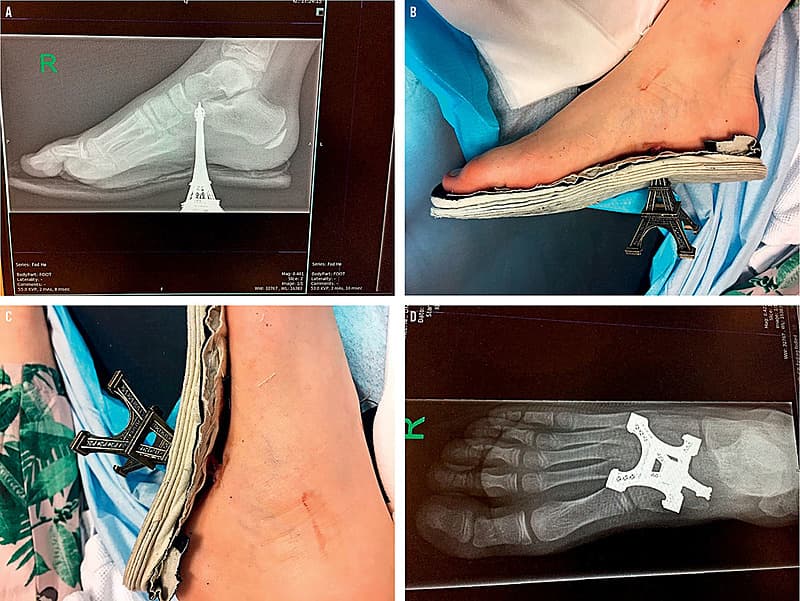

En niårig pige havde leget alene på sit værelse, hvor hun ved et uheld var trådt op på toppen af Eiffeltårnet, en mindre messingsouvenir, som hendes far havde medbragt fra Paris. Eiffeltårnet havde, ud over pigens maosutsko, gennemtrængt hud, subcutis og formodentlig m. abductor hallucis. En røntgenoptagelse verificerede, at Eiffeltårnet var endt lige medialt for talonavicularleddet. Pigen og hendes forældre var naturligvis meget påvirkede af situationen, men på skadestuen lykkedes det hurtigt i en kort rus af peroralt givet midazolam, oxycodon og lattergas at lægge en lille lokalbedøvelse. Herefter kunne Eiffeltårnet fjernes ved let traktion og rotation – nemt og smertefrit. Såret blev skyllet med rigeligt saltvand og påsat tør plasterforbinding. Pigen var i stand til at bevæge sine tæer normalt, og der blev fundet normale neurovaskulære forhold. En røntgenkontrol var uden tegn på resterende fremmedlegemer, frakturer eller luksationer af fodrodsknogler. Pigen blev sat i profylaktisk penicillinbehandling og kom til kontrol efter tre dage, hvor såret var begyndt at hele, og hun havde det godt. Som ende på historien, desuagtet hvordan hun kom derop, kan pigen formentlig som den eneste i verden sige, at hun har stået på toppen af Eiffeltårnet uden selv at have været i Paris.